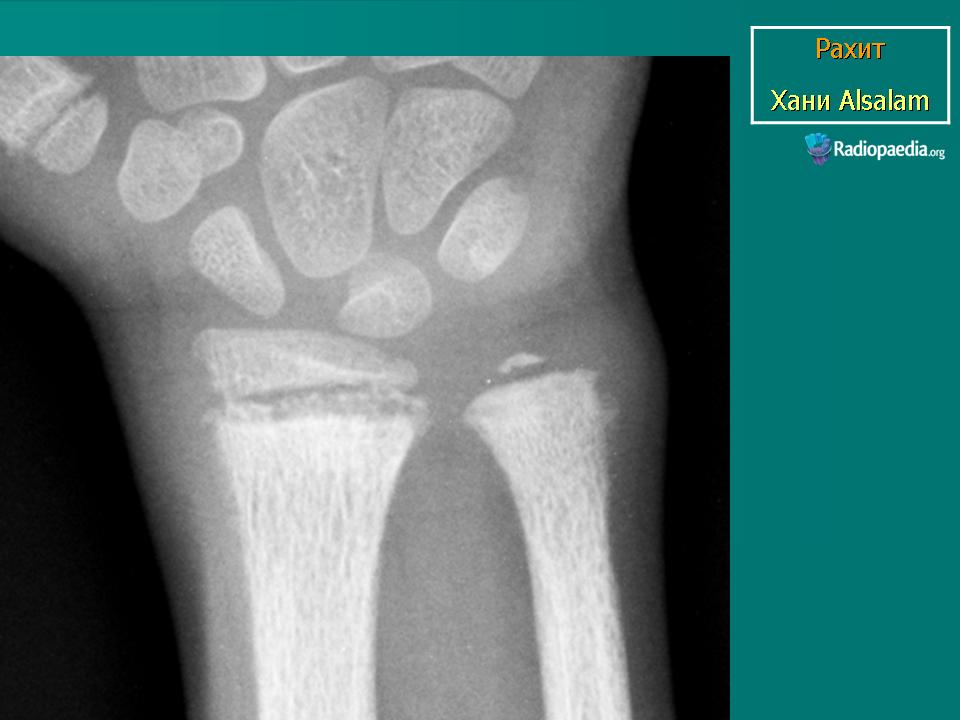

Рентгенологическое исследование позволяет уточнить диагноз, выявить тяжесть заболевания рахитом, стадию болезни, динамику процесса, действенность терапевтических средств.

Одним из первых признаков обеднения костей солями кальция является остеопороз костей, их малая контрастность. Патология энхондрального окостенения на ранних стадиях болезни проявляется в виде небольшого разрыхления зоны предварительного обызвествления, особенно в ее средней части. На уровне росткового хряща возникают участки более светлых включений. Постепенно четкость зоны роста теряется и на высоте цветущего рахита граница между эпифизарным хрящом и метафизарной костью исчезает, костные балочки свободно, в виде отдельных волосков, кисточки или бахромы, заканчиваются по направлению к эпифизу и образуется широкая, неоднородная рахитическая зона. Метафиз увеличивается в диаметре и приобретает характерную бокаловидную форму. Ввиду продолжающегося роста эпифизарное ядро все дальше отодвигается от метафиза, прозрачная для рентгеновских лучей рахитическая зона увеличивается. Ядро окостенения эпифиза также поротично, прослеживаются только наиболее толстые трабекулы, контуры его неровны, особенно со стороны, обращенной к метафизу. В очень тяжелых случаях тень ядра может полностью исчезнуть.

В области диафиза костей определяется истончение коркового вещества, контуры его со стороны костномозгового канала и особенно снаружи делаются нечеткими, вследствие откладывания остеоидно-го вещества появляется продольная слоистость, соответствующая разъединенным пластинам и несколько напоминающая периостит.